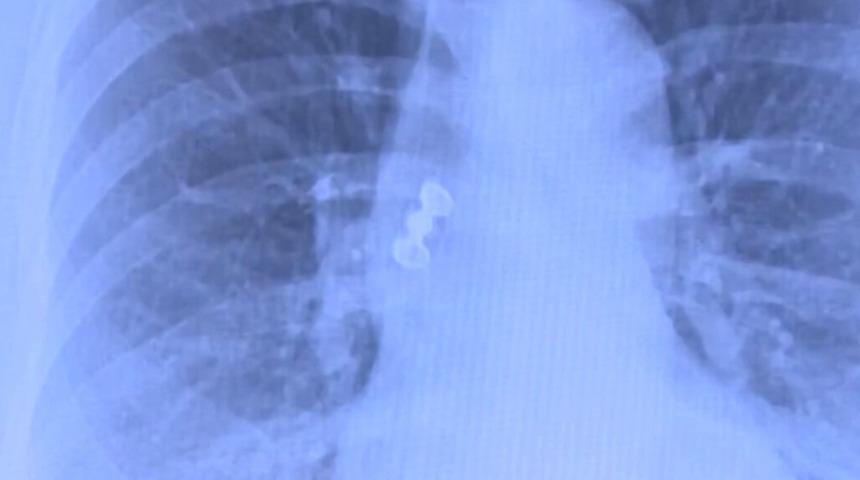

Üç dişten oluşan kaplama köprünün solunum yoluna kaçarak akciğere aspire edildiği (yutulan maddenin soluk borusuna ya da akciğerlere girmesi) belirlendi. Durumun ciddiyeti üzerine hasta yatırılarak tedavi süreci başlatıldı.

Göğüs Cerrahisi Uzmanı Prof. Dr. Levent Alpay TRT Haber'e yaptığı açıklamada, görüntülemede kaplama dişin solunum yoluna kaçtığını net şekilde gördüklerini ve acil müdahale kararı aldıklarını belirtti. Prof. Dr. Alpay, bu tür vakalarda genellikle yabancı cismin mideye kaçmasının daha sık görüldüğünü, solunum yollarına aspirasyonun ise oldukça nadir olduğunu belirtti.